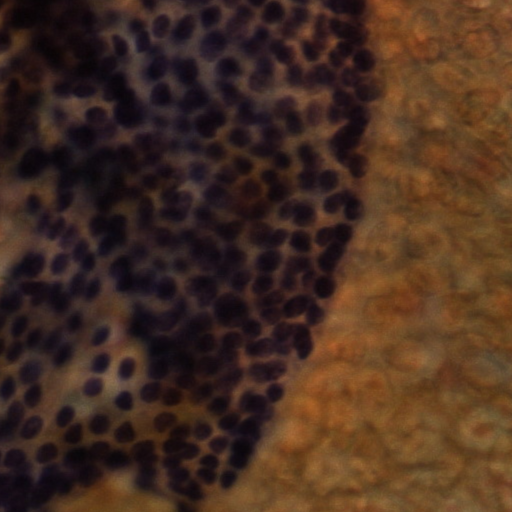

Automatic follicular area segmentation for thyroid WSIs faces many challenges due to the following difficulties. Firstly, the data size of the WSI is too large for computers to handle at one time. Secondly, after Pap staining, a large difference between the slides occurs. Figure 1 shows the staining of different slices. It can be seen that the stainings of different slides vary greatly. Besides, the follicular cells are usually tightly wrapped by the massive colloid areas, which makes follicular segmentation much harder.